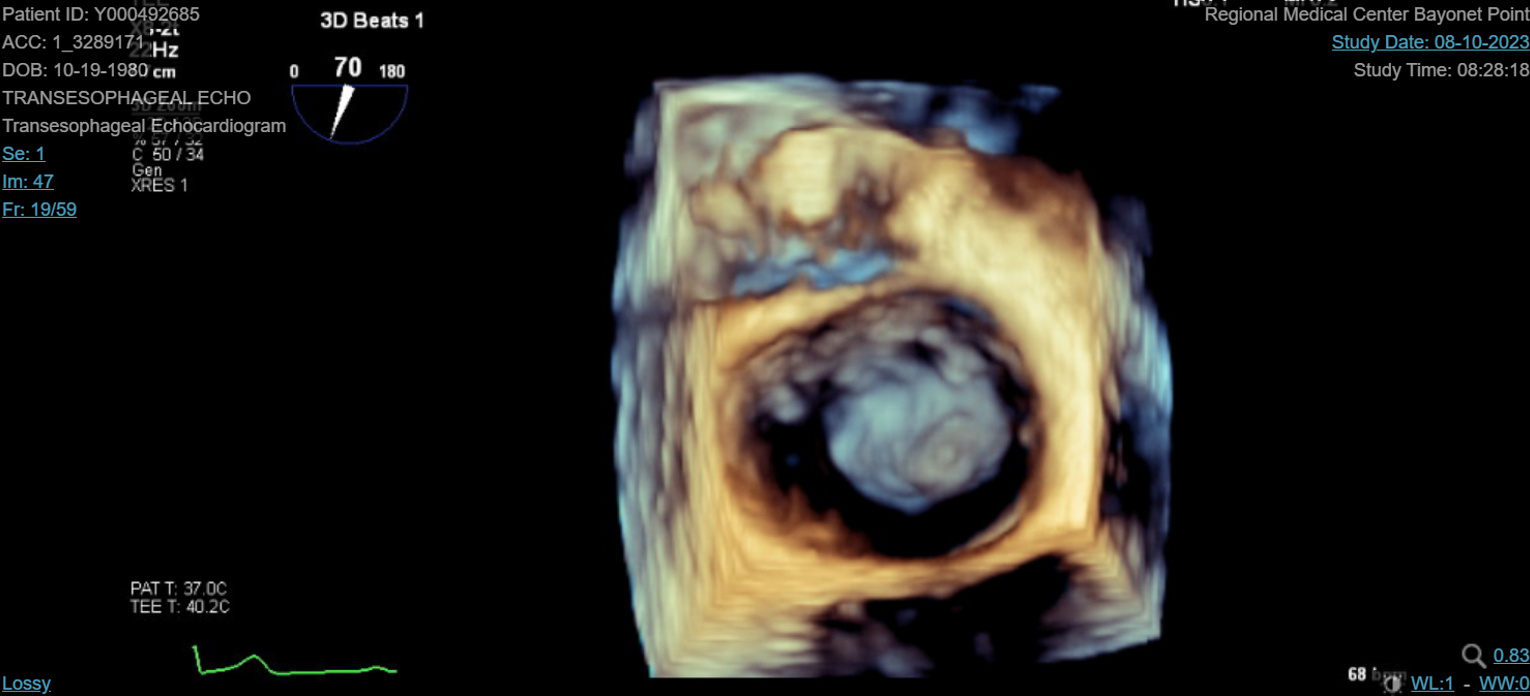

Abstract Body (Do not enter title and authors here): We describe a 42-year-old female with a past medical history significant for antiphospholipid syndrome (APS) who presented as a transfer to our facility for evaluation of stroke-like symptoms. She experienced acute onset dysarthria, left-sided weakness and a fixed rightward gaze preference. She was not a candidate for tenecteplase due to outpatient direct oral anticoagulant therapy. Computed tomography (CT) imaging of the head confirmed an acute infarct to the middle cerebral artery territory. She was taken for an emergent mechanical thrombectomy which she tolerated well. Repeat CT imaging ruled out hemorrhagic conversion. Transthoracic echocardiography revealed a 1.3 cm x 1.2 cm spherical mobile mass on the mitral valve, associated with a moderate to severe mitral regurgitation that was confirmed by transesophageal echocardiogram. The patient's respiratory status unfortunately declined and was consequently intubated. Blood cultures were negative and there was no history of intravenous drug use. The vegetation was considered marantic, representing nonbacterial thrombotic endocarditis (NBTE) secondary to APS and medication nonadherence. Cardiothoracic surgery offered surgical valve replacement after clinical recovery on an outpatient basis. She was subsequently extubated, transitioned to warfarin as recommended by hematology, weaned off supplemental oxygen, and discharged to inpatient rehab.